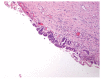

Cystic hepatic neoplasms are rare tumors, and are classified into two separate entities: mucinous cystic neoplasms (MCNs) and intraductal papillary mucinous neoplasms of the bile duct (IPMN-B). We report the case of a 56-year-old woman who presented with abdominal pain and jaundice due to the presence of a large hepatic multilocular cystic tumor associated with an intraductal tumor. Partial hepatectomy with resection of extrahepatic bile ducts demonstrated an intrahepatic MCN and an intraductal IPMN-B. This is the first report of the simultaneous occurrence of these two histologically distinct entities in the liver.